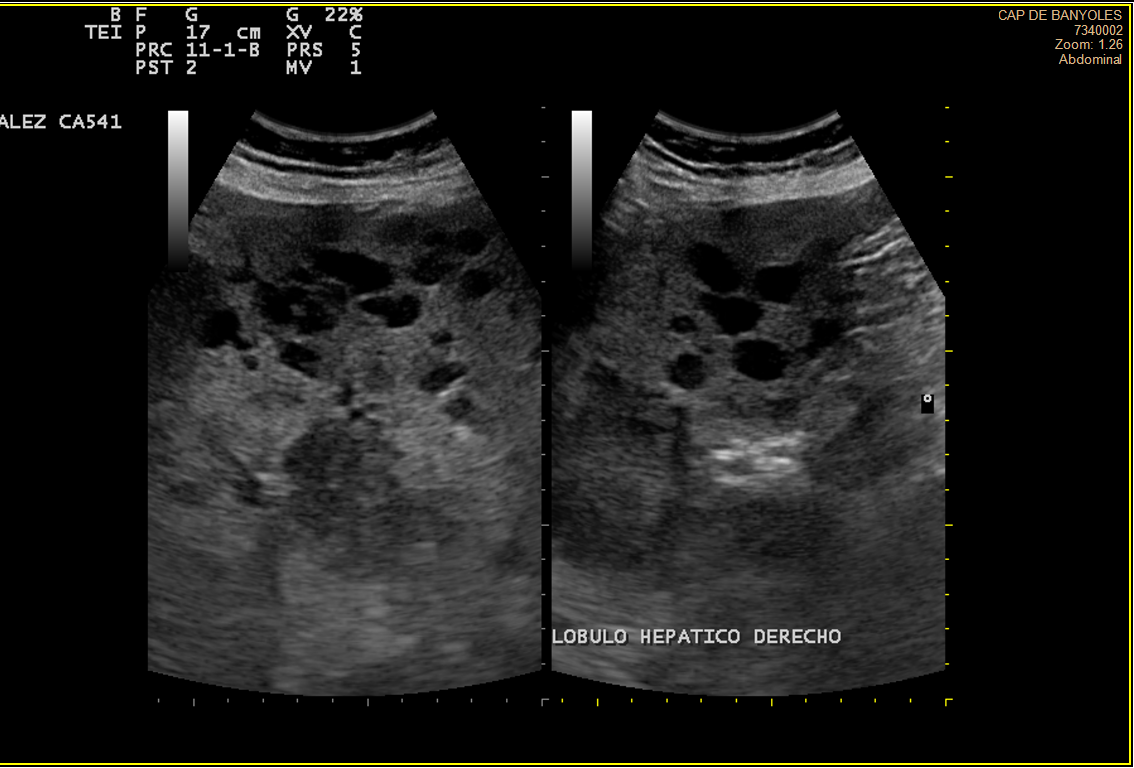

Alteración difusa de la ecoestructura hepática, presentando múltiples imágenes hipoecoicas, de diversos tamaños, resaltando una lesión en lóbulo hepático derecho de 3cm, tabicada y con ecos en su interior, con componente vascular asociado. Vesícula de aspecto normal.